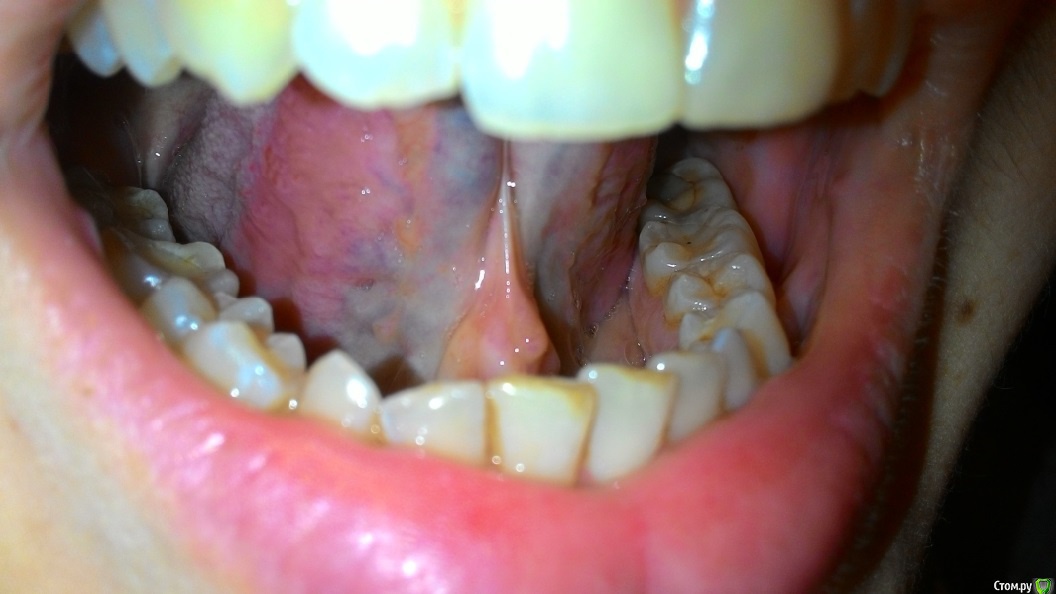

Пузырьки на уздечке под языком

На уздечке под языком у меня образовалось 2 пузырька.

28 декабря почувствовала, что как будто под языком что-то есть и оно мешается. Увидела эти пузырьки. Не болят.

29 декабря поехала снимать швы. Снимал другая доктор (мой был уже в отпуске), показала ей эти пузырьки, она сказала, что на вид пока не страшно, но что это - ей не понятно. Она показала меня еще другому доктору, та тоже сказала, что ничего страшного не видит, но толком не понимает, что это, порекомендовала наблюдать.

03 января - пузырьки сохраняются.